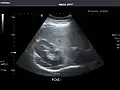

Right kidney -